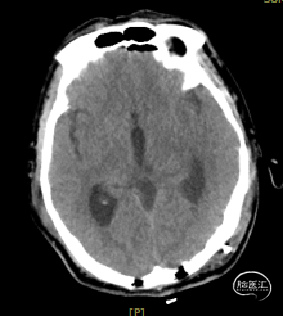

术后1天复查CT

术区无出血,脑室系统较术前显著缩小,脑积水缓解。